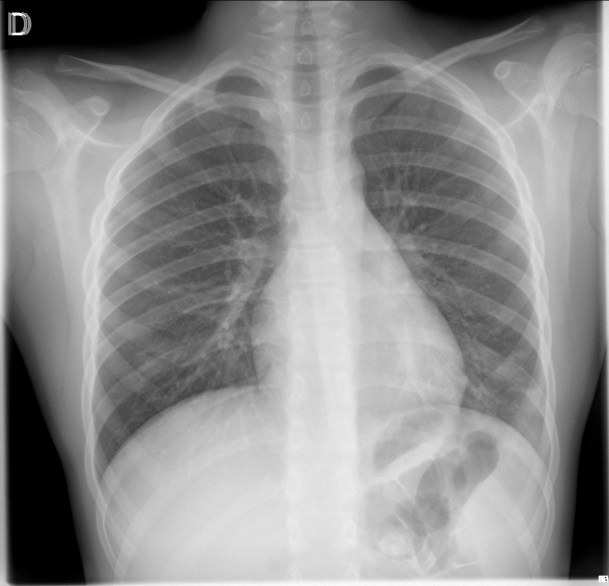

CASO: sospecha de neumonía.

Hallazgos:

- En un principio podríamos decir que existe un aumento de densidad retrocardiaco que podría ser compatible con condensación neumónica a dicho nivel, sin embargo estamos ante una placa poco inspirada, lo cual puede llevarnos a cometer errores diagnósticos.

- Se recomendó volver a realizar la radiografía, observar a continuación:

Ya no se observa el aumento de densidad retrocardiaco, la placa es normal.

INSPIRACIÓN: Una placa bien inspirada es aquella en la que se observar 6-7 arcos costales anteriores o 10-11 arcos costales posteriores. Lo contrario puede producir imágenes falsas de condensaciones o de seudocardiomegalia.